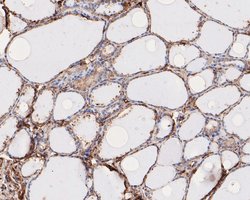

Invitrogen™ RhoGDI Polyclonal Antibody

RhoGDI Polyclonal Antibody for Western Blot, IHC (P)

| Applications | Immunohistochemistry (Paraffin), Western Blot |